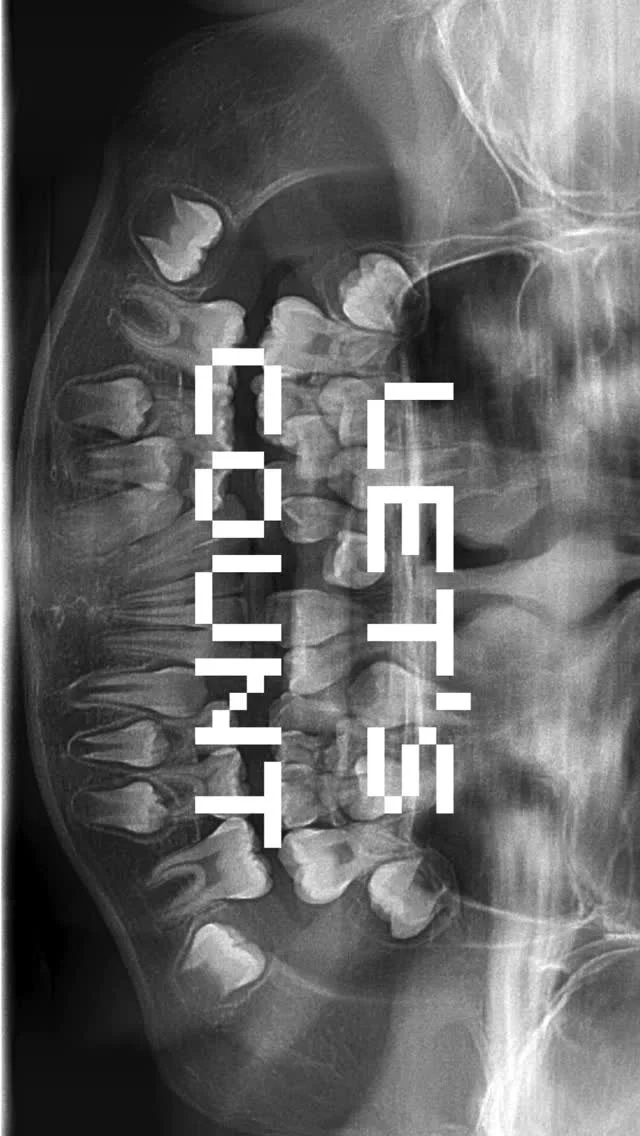

Well, thank you for taking the time! I'll keep it real: I'm a board-certified pediatric dentist and a certified balloon artist. I was top of my class in dental school even though I slept through every boring lecture there is. I like to learn but hate to study — still, that didn't stop me from reaching my goal of having you reading this!